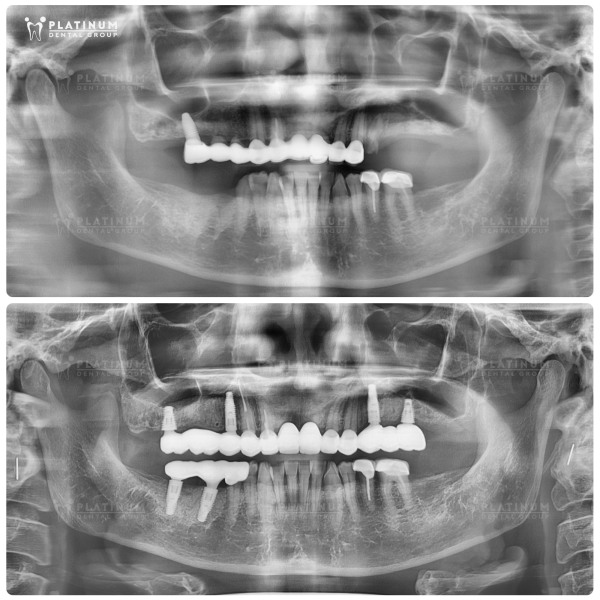

Cấy ghép implant toàn hàm – kỹ thuật “All on 4/All on 6”

Cấy ghép Implant toàn hàm (All on 4 / All on 6) là giải pháp phục hồi tiên tiến nhất hiện nay, được nhiều chuyên gia nha khoa đánh giá cao về độ bền và tính thẩm mỹ.

Kỹ thuật All on 4 hoặc All on 6 hoạt động dựa trên cơ chế sử dụng từ 4 đến 6 trụ Implant được cấy trực tiếp vào xương hàm để làm trụ nâng đỡ cho toàn bộ dãy răng phục hồi phía trên. Các trụ Implant này được đặt theo góc nghiêng khoa học nhằm tận dụng tối đa vùng xương còn tốt, giúp phân bổ lực nhai đồng đều và vững chắc. Sau khi trụ Implant tích hợp với xương, bác sĩ sẽ gắn cố định cầu răng toàn hàm, mang lại cảm giác chắc chắn, tự nhiên và gần như không khác biệt so với răng thật.

Ưu điểm:

- Khôi phục khả năng ăn nhai đến 80-90% so với răng thật.

- Ngăn ngừa tiêu xương hàm hiệu quả, giữ vững cấu trúc khuôn mặt.

- Cảm giác chắc chắn, thẩm mỹ cao, dễ thích nghi.

- Có thể phục hình tạm ngay sau khi cấy Implant, rút ngắn thời gian điều trị.

Hạn chế:

- Chi phí cao hơn so với các phương pháp khác.

- Yêu cầu bác sĩ có chuyên môn và hệ thống thiết bị hiện đại để đảm bảo an toàn và chính xác.

Tại Platinum Dental Group, kỹ thuật All on 4 / All on 6 được thực hiện bởi đội ngũ bác sĩ chuyên khoa Implant, với quy trình vô trùng tuyệt đối, công nghệ chẩn đoán hình ảnh 3D và hệ thống phục hồi chuẩn quốc tế. Cô chú anh chị sẽ được tư vấn phương án cá nhân hóa, đảm bảo hiệu quả phục hồi toàn diện và an toàn lâu dài.